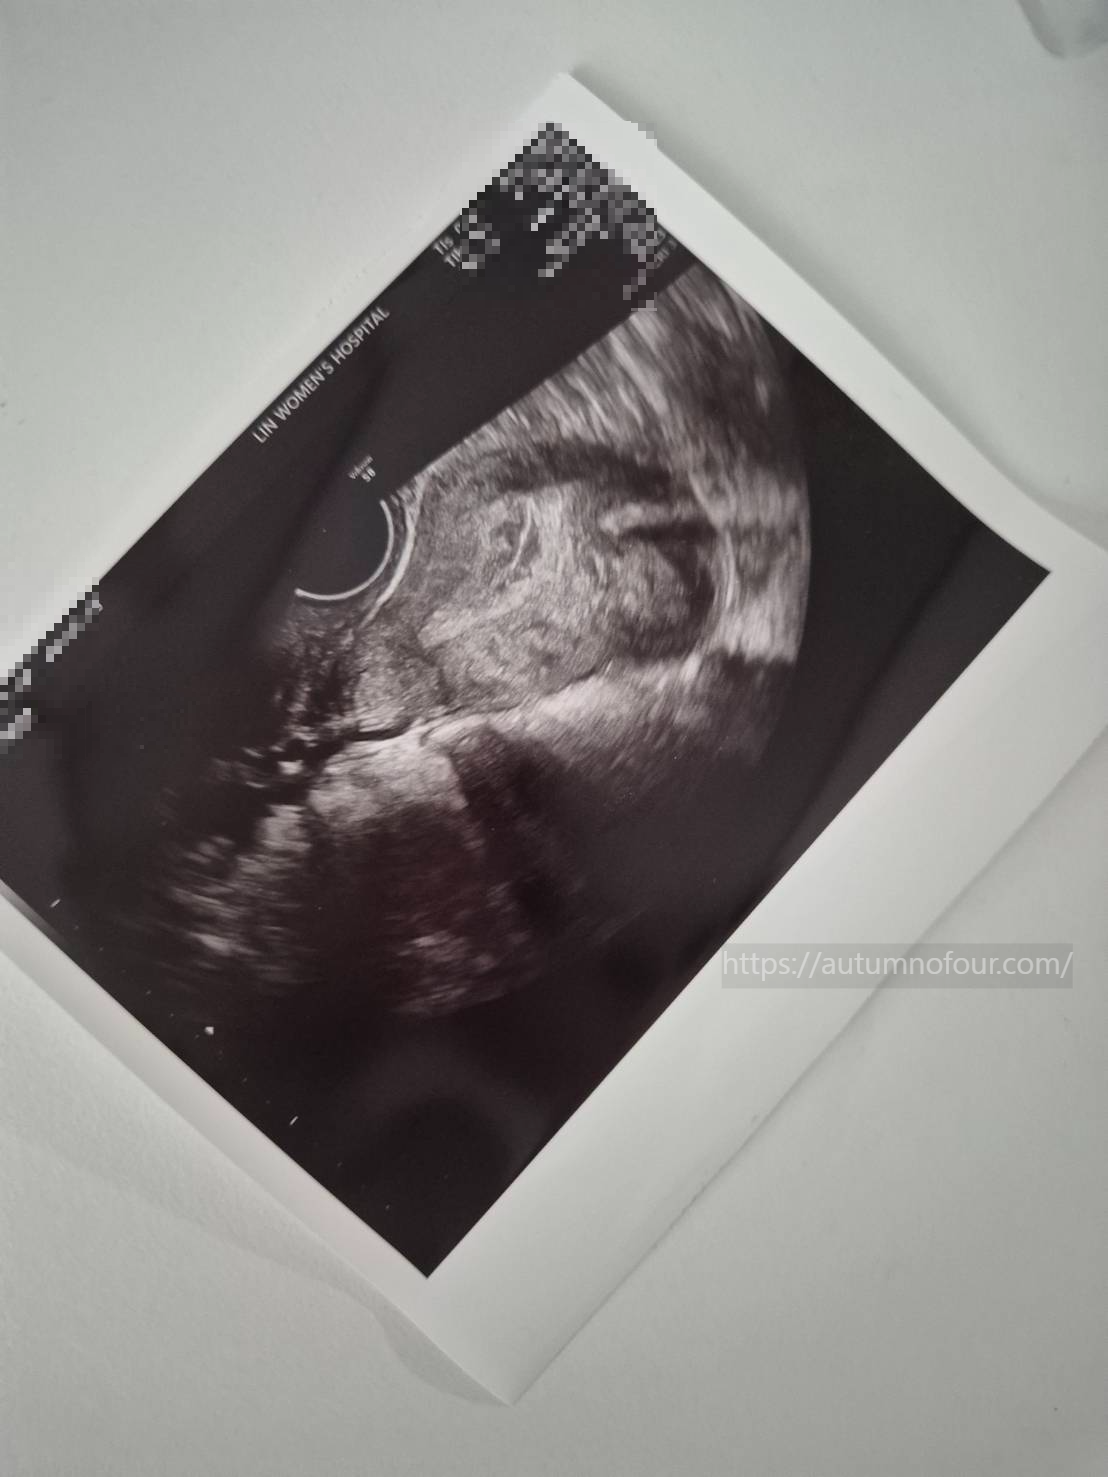

1. 오늘은 자궁 내막 두께가 잘 자라고 있는지 확인하는 날로

혹시나 적정 두께가 되지 않았다면 추가 시술이 필요하기에 2시간 정도 여유를 가지고 오라고 안내해주셨다.

원장님께서 현재로서 자궁 두께가 7~11MM정도가 되어야 적당하다고 하셨는데

아주 다행히도 나는 9MM라 추가 시술은 하지 않아도 될 거라고 하셨다.